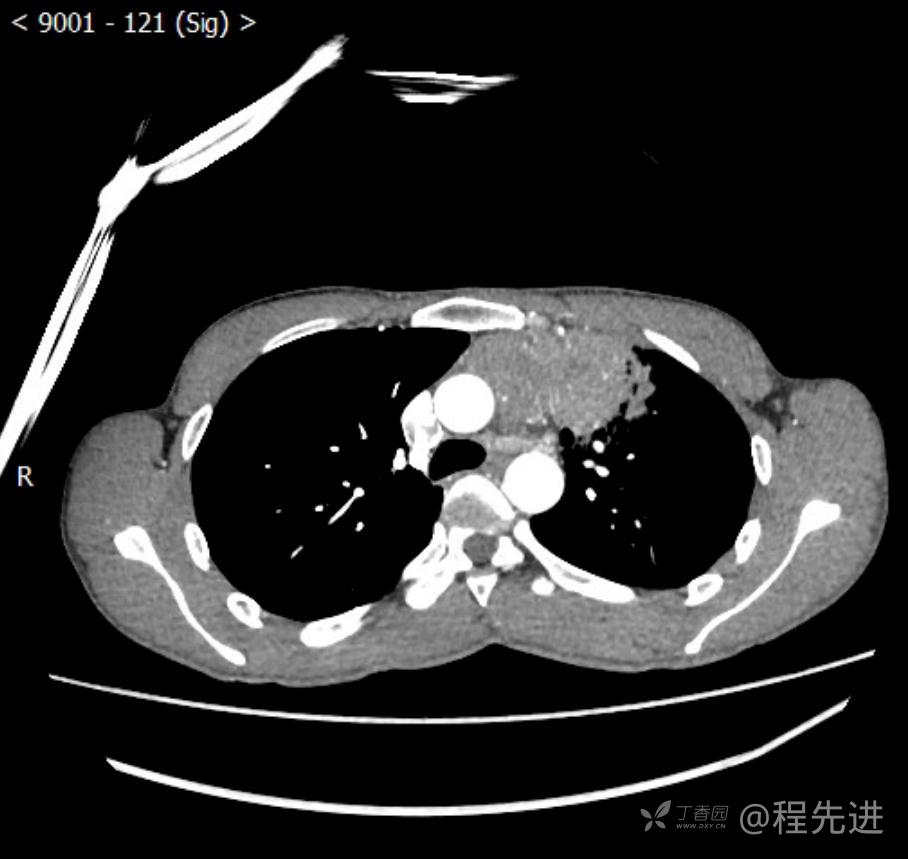

主诉:反复咳嗽1月,发现“纵隔”占位半月,乏力10余天。

现病史:患者1月前无明显诱因出现咳嗽,以夜间为著,伴有少量白痰,无发热,无胸痛、咯血,无痰中带血,未予重视,半月前外院行胸部CT检查发现“左前上纵隔”占位,未予进一步检查及治疗。近10余天自觉乏力,逐渐加重。